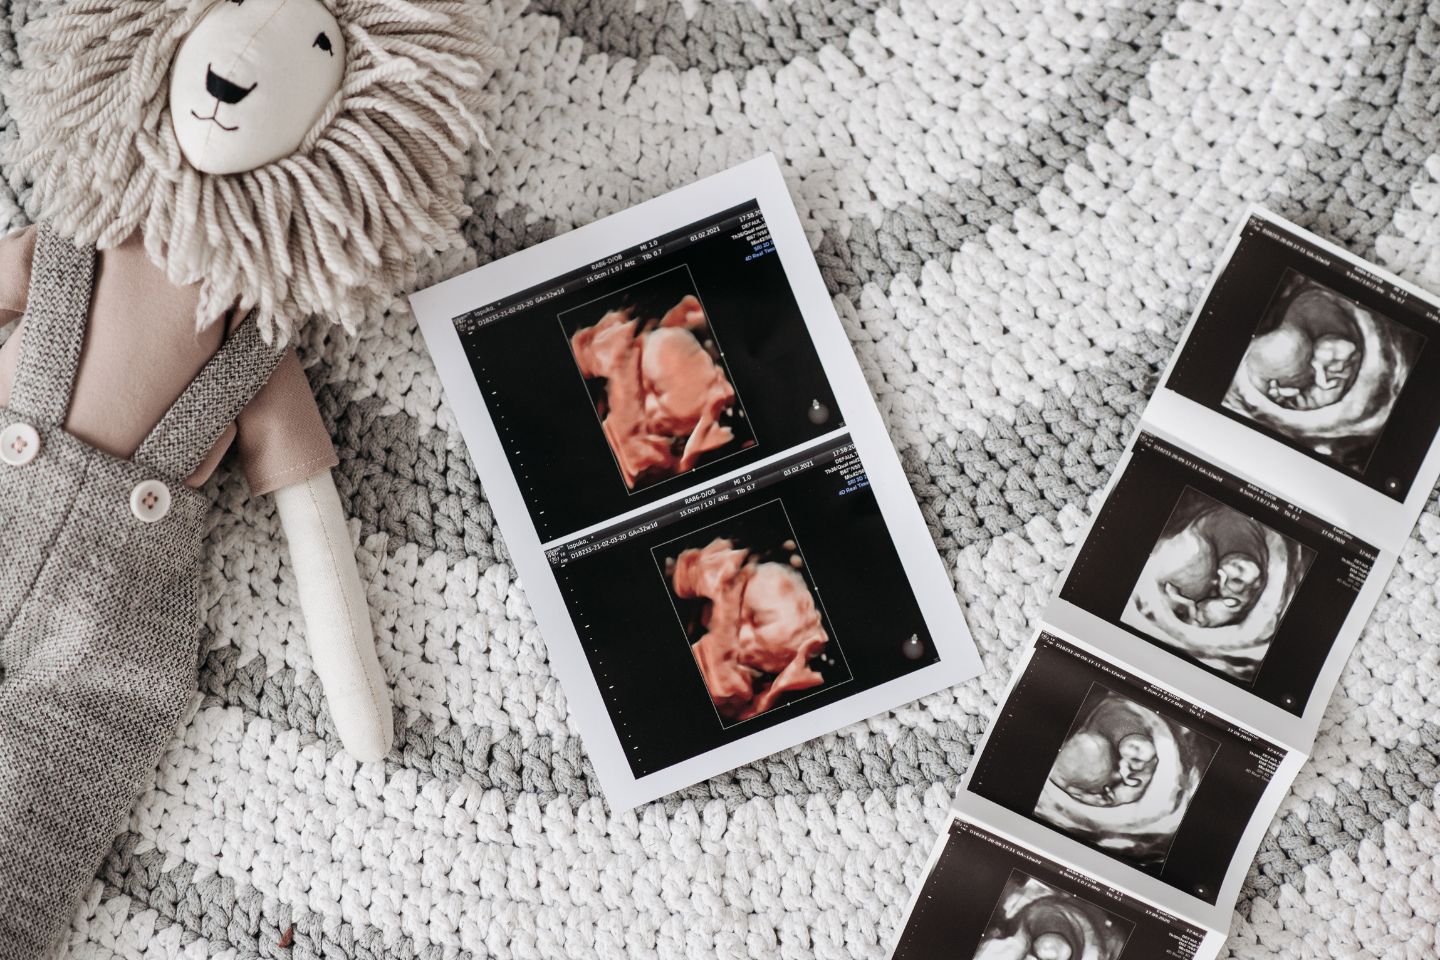

Das erste Mal die kleinen Hände des ungeborenen Kindes sehen, zum ersten Mal den Herzschlag hören, zu Hause dann das kleine Ultraschallbild an den Kühlschrank pinnen: Das sind Momente, die werdende Eltern wohl niemals vergessen. Seit den späten 1970er Jahren gibt es die Möglichkeit, ungeborene Babys via Ultraschall zu sehen und zu untersuchen. Als Teil der Vorsorge gehören drei große Termine während der Schwangerschaft dazu: Ein Termin pro Trimester. Die Kosten dafür übernimmt die Krankenkasse. Sollte es im Laufe der Schwangerschaft medizinische Gründe geben, weitere Ultraschall-Untersuchungen vorzunehmen, beispielsweise bei einer Risikoschwangerschaft, trägt die Krankenkasse auch diese Kosten.

Noch bis Ende 2021 gab es die Möglichkeit, zusätzlich zu den drei großen Untersuchungen, weitere Ultraschalltermine zu vereinbaren. Beispielsweise, um das ungeborene Kind mit Hilfe eines 3 D-Ultraschalls noch intensiver zu beobachten. Dies fiel unter so genannte IGe-Leistungen in der ärztlichen Praxis. Die neue Strahlenschutzverordnung verbietet aber das zusätzliche Baby-Kino. Im Gesetzestext heißt es: „Bei der Anwendung von Ultraschallgeräten zu nicht-medizinischen Zwecken darf ein Fötus nicht exponiert werden.“ Begründet wird dies damit, dass es sich bei dem Fötus um eine schutzbefohlene Person handele. Durch die neue Strahlenschutzverordnung soll das Baby vor unnötigen Einwirkungen geschützt werden, da das “Baby-Kino” für den Fötus und dessen Gesundheit keinen weiteren Nutzen darstellt.

Dies ist der letzte große Ultraschall während der Schwagerschaft. Euer Ungeborenes wird noch einmal ausgemessen. Kindslage wie auch Lage der Plazenta werden überprüft. Beides ist wichtig für eure Geburtsplanung und den Ablauf. Doch keine Sorge: Sollte euer Kleines bei diesem Termin noch nicht mit dem Köpfchen nach unten liegen, müsst ihr euch nicht stressen. Viele Babys drehen sich meist erst gegen Ende der Schwangerschaft, manchmal auch erst kurz vor der Geburt. Einige Ärzt:innen haben übrigens für diesen Termin ein 3 D-Ultraschallgerät, das es euch ermöglicht, euer Wunder in all seiner Pracht und mit vielen Details zu bewundern.